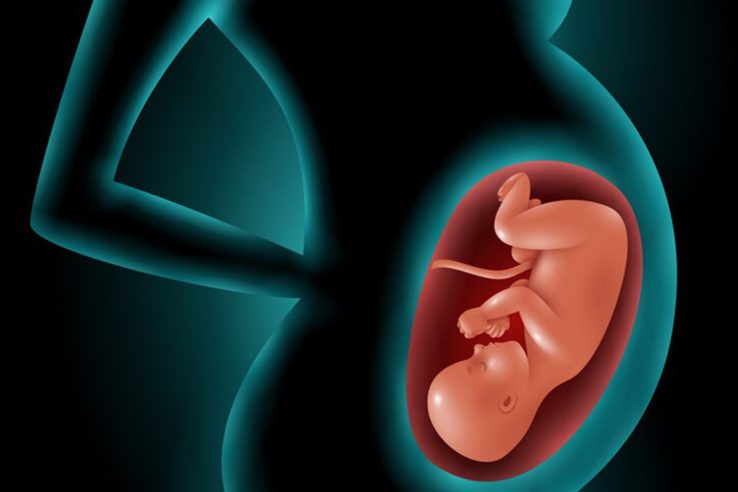

Infertility is a condition affecting millions of people worldwide, often in silence and solitude. For many couples, the path to parenthood is not always straightforward, and understanding how common infertility…